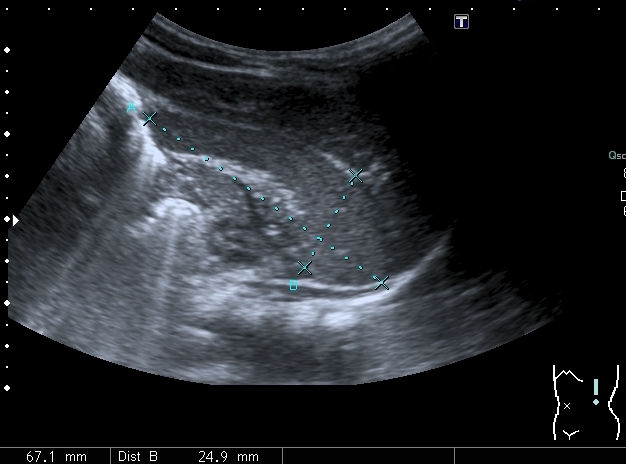

Левая доля

Левая доля прилежит к селезёнке, оттесняет её вниз и дорзально

Паренхима печени -гиперэхогенная , неоднородная, практически полностью замещена нодулярными образованиями, некоторые из них с "гало" и кальцификацией